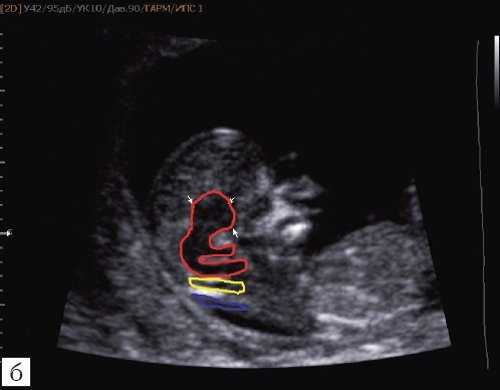

Как сказано выше, имеет значение и измерение ножек "осьминожки", так среднее значение диаметра нижней ножки, т.е. IV желудочка в зависимости от КТР в срок 11-14 недель варьирует от 1,5 до 2,5 мм (рис. 4).

Рис. 4. Измерение и взаимоотношение ножек "осьминожки" - ствола мозга и IV желудочка у плода, беременность 12 недель.

Измерение ножек "осьминожки".

Красный цвет - диэнцефалон (таламус), со стволом мозга (верхняя ножка) и IV желудочком (нижняя ножка); желтый цвет - большая цистерна головного мозга; синий цвет - воротниковое пространство.